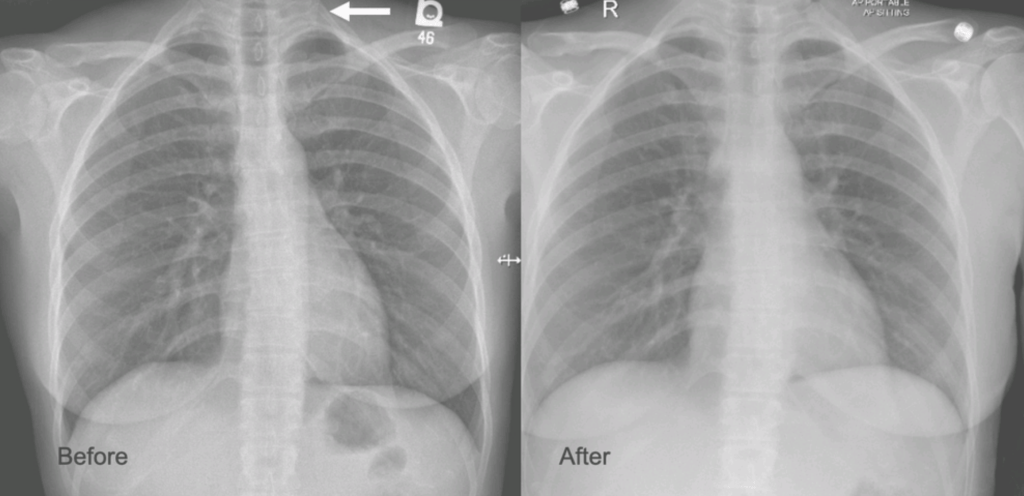

This patient from the images above is a middle aged man who competes in triathalons and who noted sudden onset of discomfort and heaviness and pain in his left arm. Ultrasound revealed DVT in his axillosubclavian veins extending into his brachial veins and he was started on anticoagulation. He had been on anticoagulation for about a month by the time he came to my clinic. On examination, he had a prominent superficial veins on his shoulder, but otherwise had a normal examination. He did not have arterial obstruction on TOS (thoracic outlet syndrome) maneuvers and had no neurologic symptoms. I recommended first rib resection.

The patient did well, recovering much of his range of motion quickly with the help of physical therapy. He was taken to the angio suite and underwent venography shown below. There is an occlusion of the subclavian with outflow via collateral veins. Not seeing collaterals is as important as seeing a good angiographic result. pre intervention

Venoplasty was done to 8mm -I try not be overly aggressive here, just to break the strictures that caused the balloon to have a waist in two sections. The final result is below, with the absence of the venous collaterals. If they were still present despite an angiographically satisfactory result, I would perform IVUS to see what the problem was. In no circumstances would I place a stent at this juncture -my plan is to keep the patient on anticoagulation for 3 more months.

post intervention